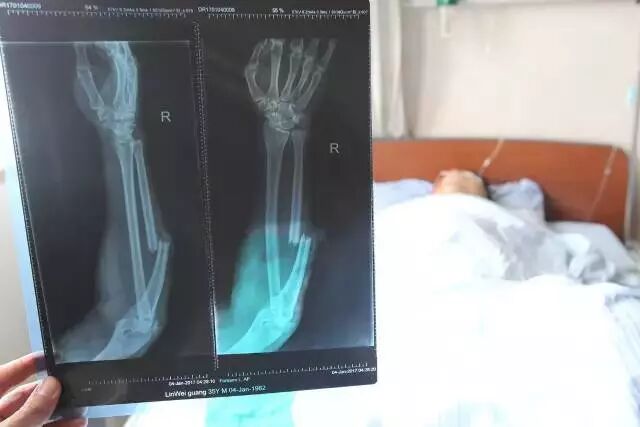

▲林伟光全身6处骨折,

其中头部、右臂、髋关节、右腿伤情较为严重。

▲林伟光正在手术,在征得医生的同意后,

拍下了林伟光手术的画面。